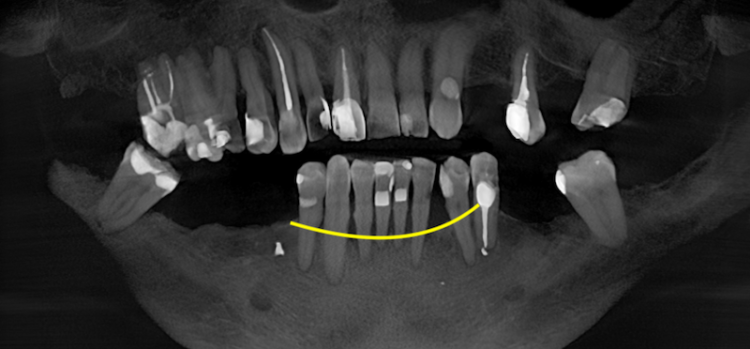

Пародонтоз — это дистрофическое заболевание тканей пародонта, то есть структур, которые удерживают зуб в челюсти. К этим тканям относятся десна, периодонтальная связка, цемент корня и альвеолярная кость. Для этого состояния характерны постепенные изменения в опорном аппарате зуба. Костная ткань медленно уменьшается в объёме, десна могут отступать, оголяются шейки зубов, появляется повышенная чувствительность. На рентгене часто видно равномерное снижение высоты кости вокруг зубов.

По внешним симптомам не всегда можно точно определить тип поражения пародонта. Окончательный диагноз устанавливают после осмотра, пародонтологического обследования и рентгенологической оценки состояния костной ткани.

Клиническое и рентгенобследование

Перед имплантацией проводят полную диагностику. Врач оценивает кровоточивость дёсен, глубину пародонтальных карманов, уровень прикрепления тканей и подвижность зубов. Далее выполняют компьютерную томографию (КЛКТ), которая позволяет измерить высоту и толщину альвеолярной кости, определить её плотность и оценить анатомические структуры — нижнечелюстной канал или гайморову пазуху.